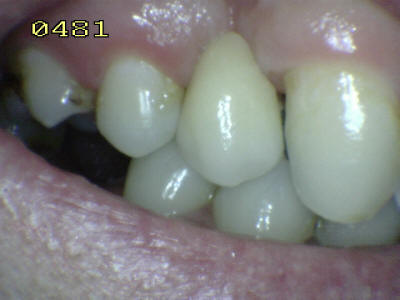

Paciente de sexo

femenino presenta un Puente Maryland de 2 piezas de metal y

acrílico con 25 años de servicio en boca.

Vista vestibular: Observe el desgaste del

acriíico en el borde cuspideo de canino y premolar

Vista palatina: el metal después de 25

años de servicio se muestra inalterable.